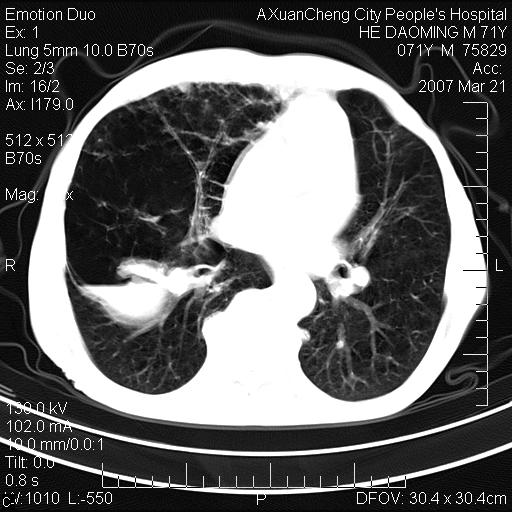

标题: CT7269:[原创] 咳嗽,咳痰,大家讨论右肺病变的部位 [打印本页]

标题: CT7269:[原创] 咳嗽,咳痰,大家讨论右肺病变的部位

1.慢支肺气肿 肺心病 肺大泡;2.叶间裂积液,前胸膜粘连

右侧相当于叶间软组织样密度ct值约50hu,请大家讨论是什么性者病变

考虑:慢性支气管炎合并全小型肺气肿、肺大泡、间质纤维化、感染,右斜裂积液。

考虑慢支,肺气肿,肺大泡,间质纤维化;右侧斜裂液气胸考虑(可能因为肺大泡破裂破入斜裂所致).

考虑病变以右上中肺多发肺大泡为主并感染。请结合临床考虑慢支肺气肿,肺心病。

1双肺慢性支气管炎并全小叶型肺气肿肺大泡2间质性纤维化3右侧斜裂积液

考虑:慢性支气管炎合并右侧全小型肺气肿、肺大泡并感染、双肺间质纤维化,右斜裂积液。

如果患者变化一下体位扫描可分辨液平与斜裂的关系。